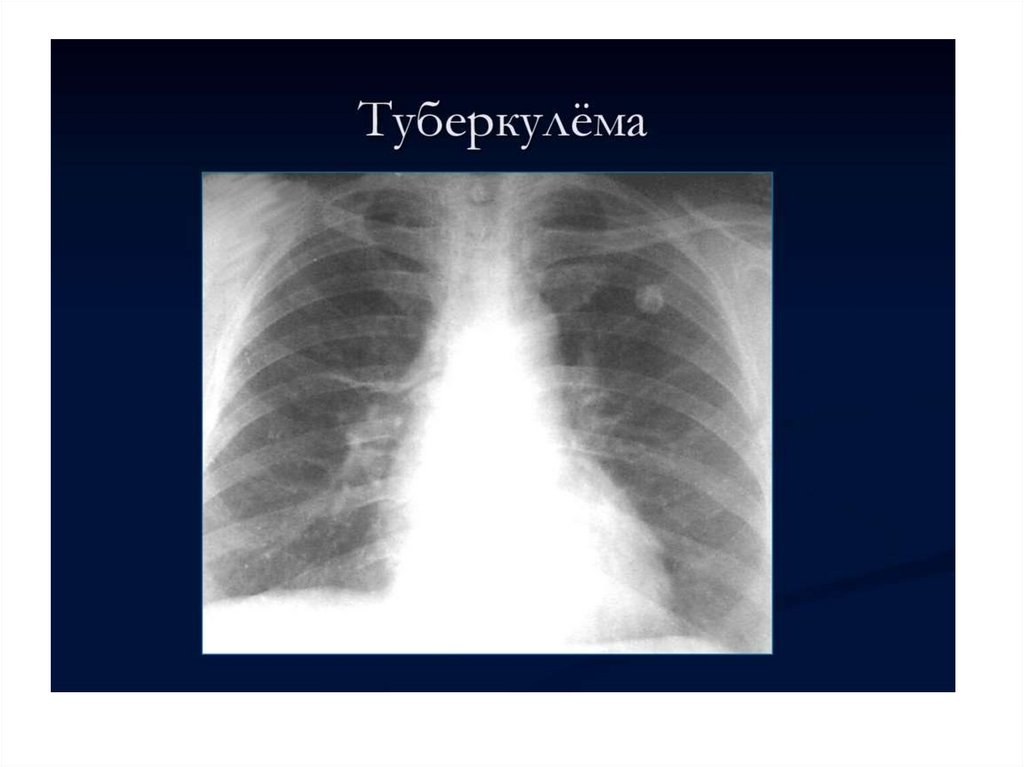

Малые формы туберкулеза легких тренинг по основным малым формам туберкулеза легких

Малые формы туберкулеза легких

тренинг по основным

малым формам туберкулеза легких